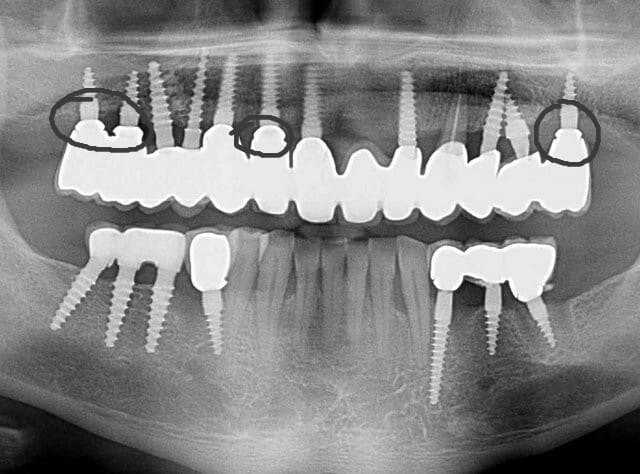

Pour ceux que ca interessent, et parce qu on a m a demandé des cas supplémentaires dans le sujet 23 implants rehabilitation totale, voici un autre cas d implantation immédiate avec la technique minimalement invasive et condensation grace aux forets.

Le patient a reçu un traitement il y a dix ans dans le maxillaire et dans le 4eme quadrant.Comme on peut le voir j´ai du extraire quelques dents au maxillaire: 35 37 et 45.

Le septum de la 37 a été foré avec un foret conique 3 faces.

J ai planté à 60 Ncm sans fracturer le septum.Juste après l opération , les prep caps en zircon ont été cémenté.La restauration définitive 34 jusqu` à 37 été fixé 2 semaines après l implantation avec implantlink (detax). Après un an, le bridge a été retiré facilement pour voir l´état de la gencive et faire une radio de contrôle.On la re ossifiction est satisfaisante et que la gencive "aime" le zircon.

Le bridge a ensuite été recémenté sans correction nécessaire du bridge.